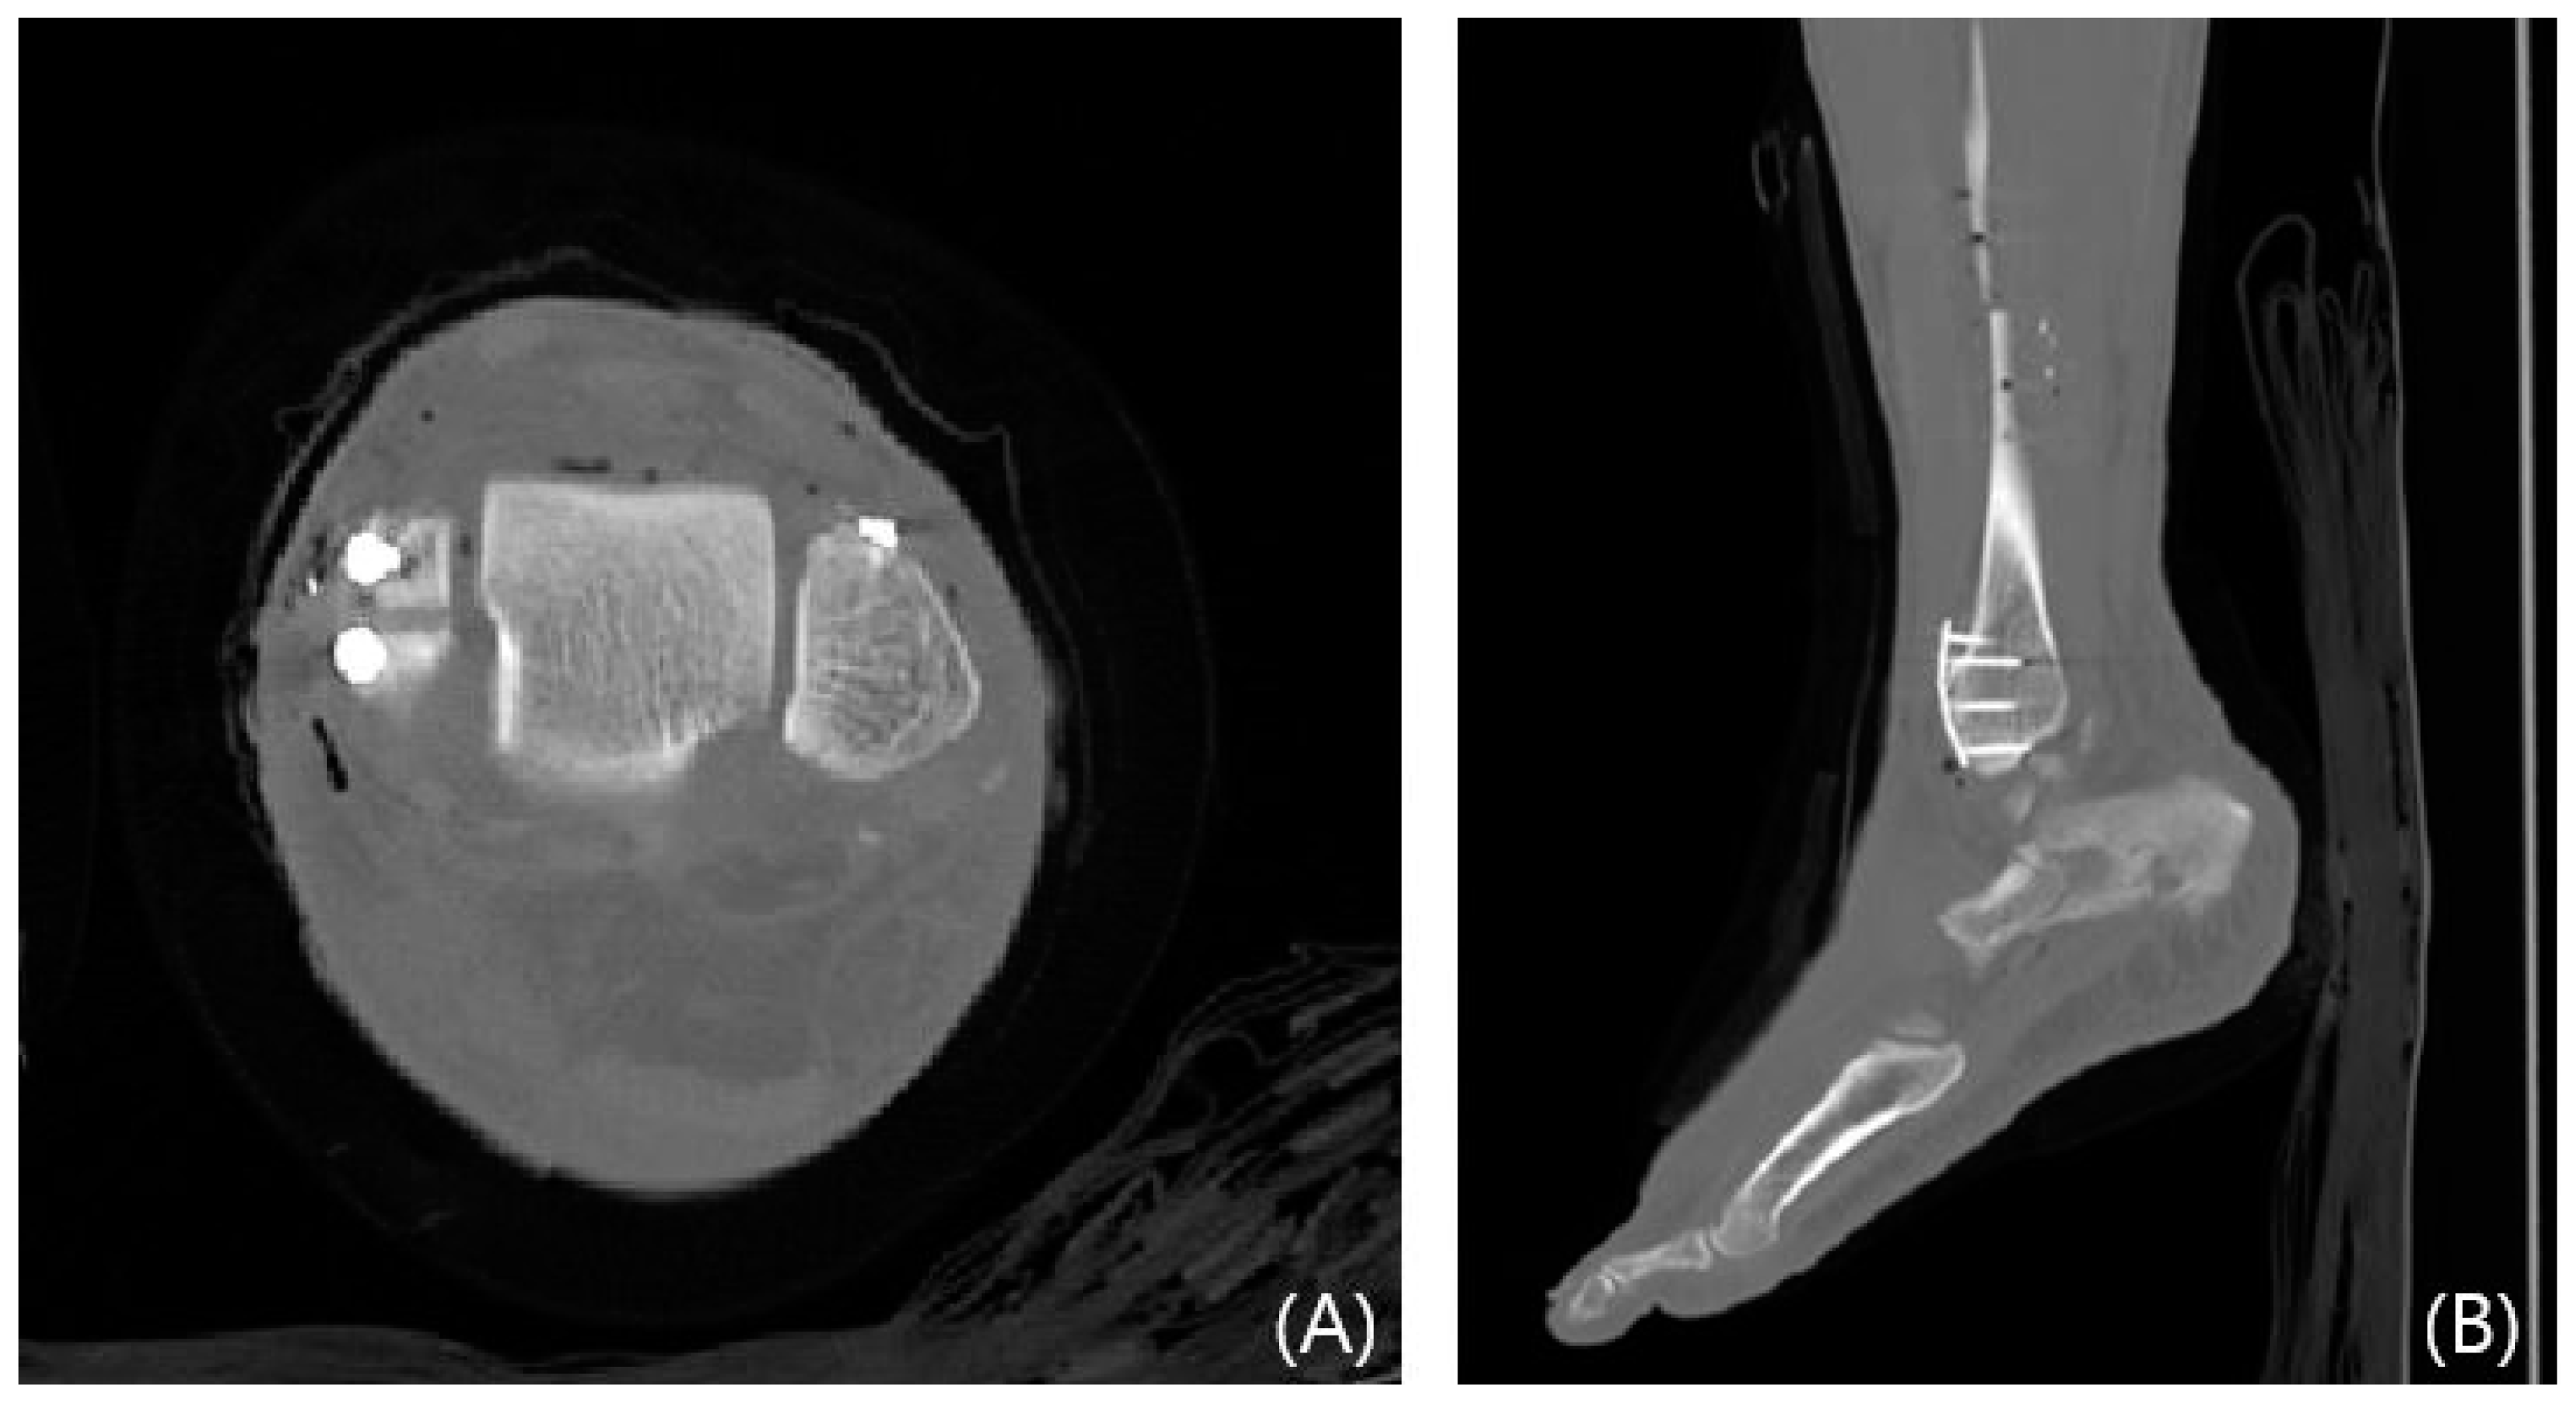

2.3. Radiological Evaluations

This study evaluated syndesmosis reduction by analyzing postoperative axial CT images captured 1 cm proximal to the tibial plafond (Table 1 and Figure 1) [16,17,18,19]. Four radiographic measurements were chosen and assessed with a PACS image viewer software (Dejaview2 version 1.0, Dongwun Information Technology, Republic of Korea). Two independent observers, blinded to patients’ clinical outcomes and current complaints, objectively evaluated the measurements. The process was repeated after a 6-week interval to ensure reliability.

Figure 6. Preoperative CT images of a 47-year-old female with a Wagstaffe fracture (red arrow). Axial (A) and sagittal (B) views.

Jcm 13 01605 g006